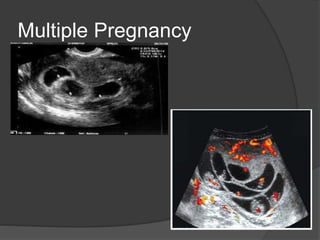

Multiple Pregnancy

 Multiple pregnancies and types of twinning depends on

the number of zygotes and timing of division and they are

:

1- Dizygotic twins : two fertilized ova and they are all

dichorionic , diamniotic

2- Monozygotic twins : the amnionicity and chorionicity

depends by the time of zygote division

- Before 3rd day post conception : diamniotic, dichorionic

- 4th-8th day post conception : monochorionic , diamniotic

- Cleavage of the inner cell mass of blastocyst after 8th day

post conception : monochorionic, monoamniotic.

- Incomplete cleavage of embryonic disc after 13th day post

conception : conjoined twins

Multiple Pregnancy  Multiplepregnancies and types of twinning depends on the number of zygotes and timing of division and they are : 1- Dizygotic twins : two fertilized ova and they are all dichorionic , diamniotic 2- Monozygotic twins : the amnionicity and chorionicity depends by the time of zygote division - Before 3rd day post conception : diamniotic, dichorionic - 4th-8th day post conception : monochorionic , diamniotic - Cleavage of the inner cell mass of blastocyst after 8th day post conception : monochorionic, monoamniotic. - Incomplete cleavage of embryonic disc after 13th day post conception : conjoined twins